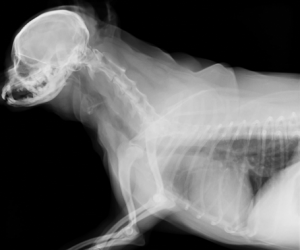

潰れた気管を確認しました。